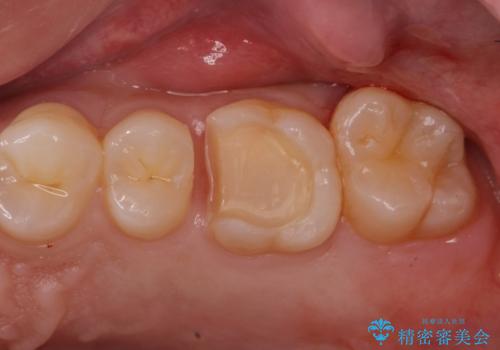

適合の良い詰め物が入りました。